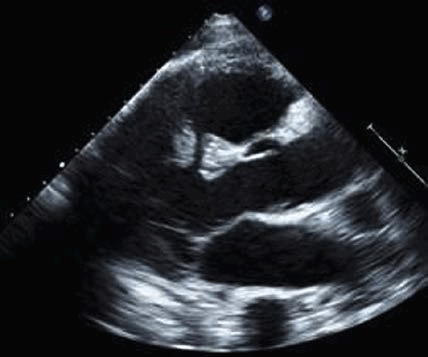

Другой причиной внезапной артериальной гипотензии и отека легких у пациента в пери- и постинфарктном периоде является разрыв межжелудочковой перегородки. Дефект заставляет насыщенную кислородом кровь течь из левого желудочка в правый и смешиваться с деоксигенированной кровью. Дефекты межжелудочковой перегородки (ДМЖП) могут возникать в переднем отделе перегородки (лучше всего видно в парастернальных окнах) из-за переднего ИМ или в нижнем отделе перегородки (лучше всего в апикальном четырехкамерном и субкостальном окнах) в результате нижнего ИМ. Оба типа ДМЖП могут быть проверены на предмет использования парастернальных окон по короткой оси. Использование цветного допплера имеет важное значение для обнаружения этих разрывов на эхокардиографии, потому что разрыв ткани часто имеет щелевидную или змеевидную форму и может быть плохо заметен на одном только 2D-изображении.

- Получите стандартный парастернальный вид сердца по длинной оси, показывающий левый желудочек (ЛЖ) и правый желудочек (ПЖ). Имеет ли межжелудочковая перегородка нормальную толщину и сокращается ли она во время систолы?

- Поместите цветное допплеровское окно на межжелудочковую перегородку, особенно на любые акинетические участки или сегменты с пропаданием эхо-сигнала (анэхогенные зоны). Цветовой поток слева направо, проникающий через перегородку, указывает на ДМЖП.